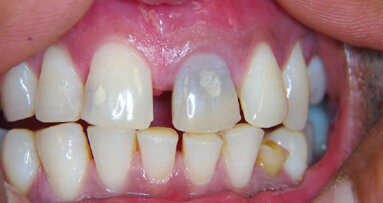

Dvě kazuistiky přímé kompozitní dostavby frontálních zubů s pomocí kompozitního materiálu Charisma Topaz (Heraeus Kulzer). Zkrácená verze – celý článek naleznete na www.stomateam.cz, nebo v časopise StomaTeam 5/2016 (pozn. red.).

Frontální výplně jsou velice individuálním typem ošetření, při němž terapeutické možnosti závisí především na velikosti defektu a estetických požadavcích pacienta. Přestože nepřímé keramické náhrady jsou vysoce kvalitním univerzálním „kouzelným“ výstupem, který umožňuje vložit estetické a funkční problémy do rukou zubního technika, vyžadují obvykle výrazně masivnější základní konstrukci než přímé kompozitní výplně a jsou také výrazně dražší. Kromě aspektu nákladů však přímé výplně skórují i z hlediska přístupu „jedné návštěvy“, tj. že pacient nepotřebuje žádnou provizorní náhradu a může jednoduše odejít domů s definitivní výplní. V zásadě totéž je možné se systémem Cerec, ale požadavky na zbytkovou hmotu zubu a náklady zde zůstávají.

Takto velké rekonstrukce funkce frontálních zubů hovoří samy za sebe díky metaanalýze zveřejněné na toto téma, které se podařilo prokázat míru průměrné roční ztráty kompozitních výplní mezi 0 až 4,1 %. Protože hlavním důvodem selhání větších výplní kavit IV. třídy bylo jejich odlomení, je prokázán význam volby stálejších kompozitních materiálů, které mají vysokou pevnost v lomu.